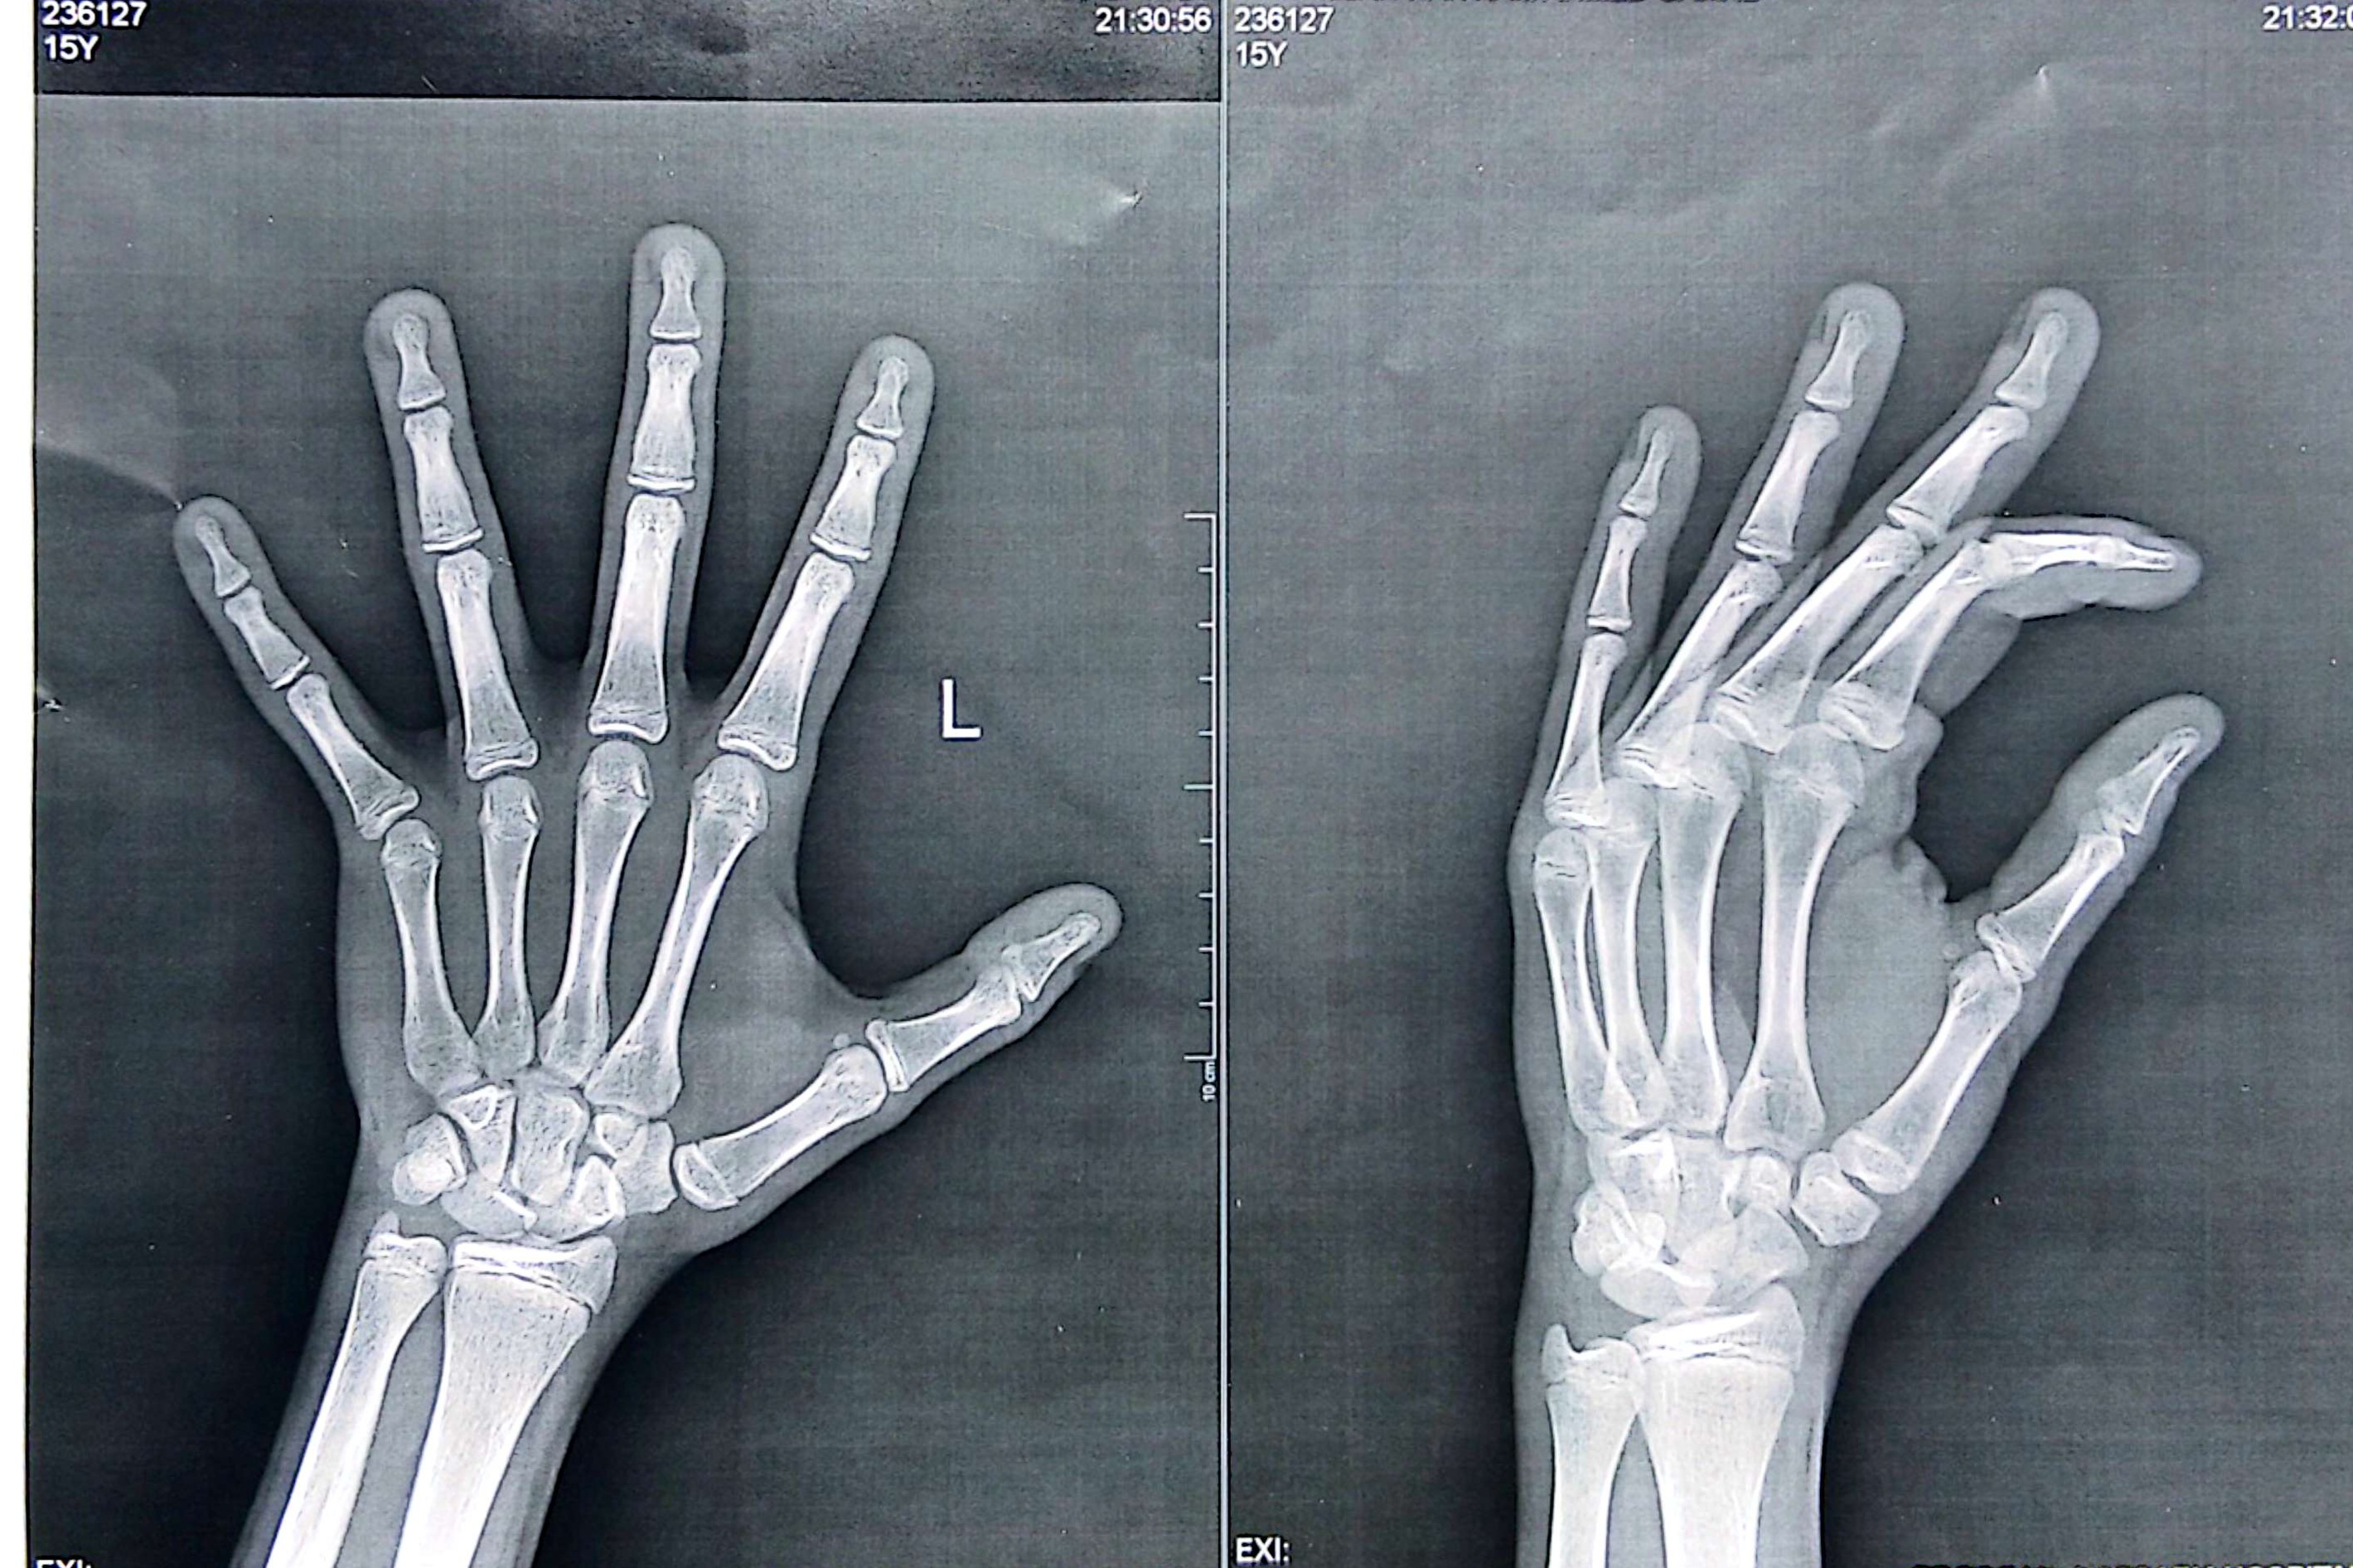

I am 15y old

18/6/2010

Pls I need help predicting my final hight and I sadly can't take peptides or hormones

(I am Egyptian)